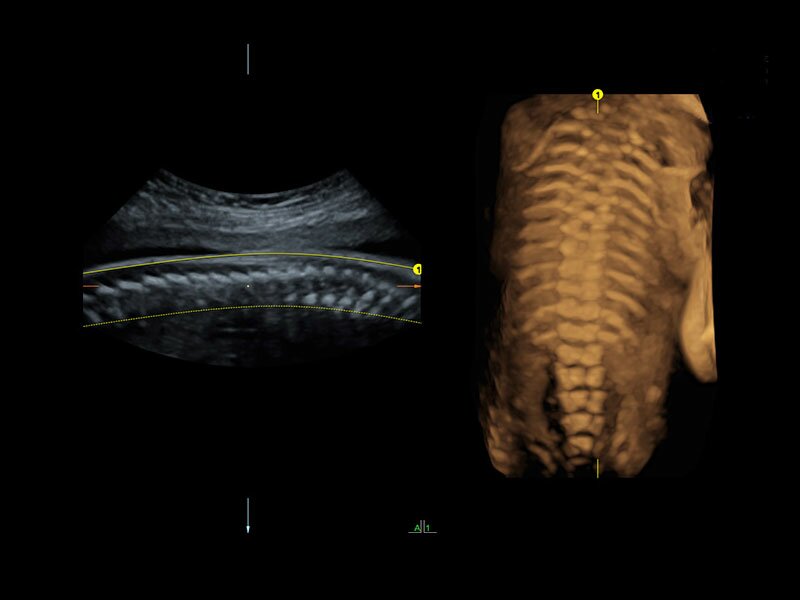

Клинические изображения

Объемное сканирование Voluson — 3D/4D вашей мечты

Объемное УЗИ на Voluson E10 — это не просто потрясающе красивая картинка, это ценный инструмент получения дополнительной информации при обследовании женщин.

Voluson E10 поддерживает инновационные технологии формирования изображений — HDlive Silhouette и HDlive Flow, которые позволяют увидеть мельчайшие детали. Алгоритм SonoRenderlive упрощает рабочий процесс и дает возможность реконструировать изображение поверхностей, определяя область перехода между тканью и жидкостью.

• SonoRenderlive

• Улучшает объемную визуализацию за счет автоматического определения линии начала реконструкции при изображении поверхностей. При исследовании в режиме 4D функция SonoRenderlive непрерывно обновляет положение исходной линии с учетом движений плода.

Инновационные датчики

УЗИ аппарат Voluson E10 поддерживает работу широкой номенклатуры датчиков, в том числе специализированные высокочастотные датчики для выполнения самых сложных исследований.

Новая система совместима с множеством существующих датчиков Voluson, а современная архитектура позволяет в полной мере реализовать их диагностический потенциал, обеспечивая превосходное качество и высокую четкость изображений.